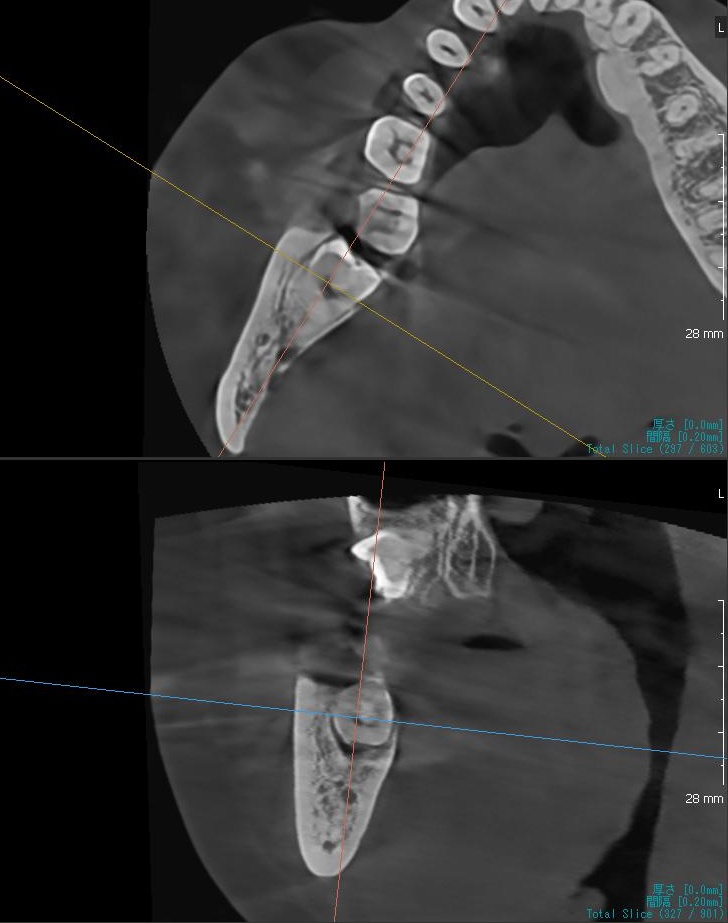

さらに、下顎の親知らずは下歯槽神経に非常に近いところに生えている場合もあるため、CTも撮影し詳しい解析を行います。

親知らずが生えている位置が、神経に近い、あるいは神経に当たっている場合は、大きな病院に紹介する場合もあります。

親知らずの根っこは下歯槽神経から近い距離にありますが、抜歯は可能との診断でした。